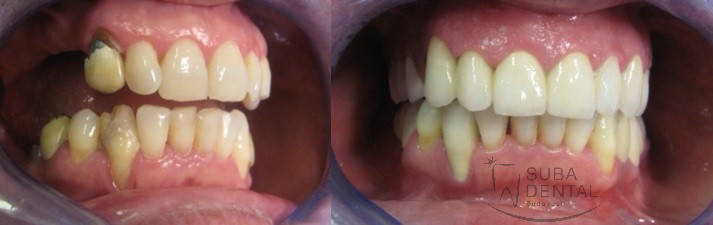

Before After